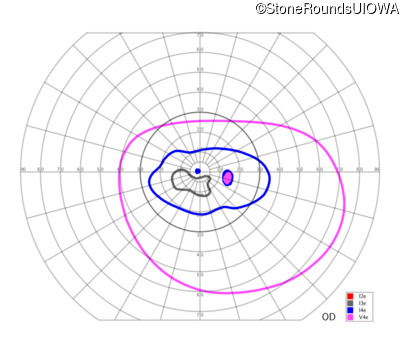

Congenital Stationary Synaptic Dysfunction (IA2g)

Congenital Stationary Synaptic Dysfunction (IA2g)

| Congenital Stationary Synaptic Dysfunction | CABP4 | Arg49Stop CGA>TGA | IVS1+1 G>T | AR |